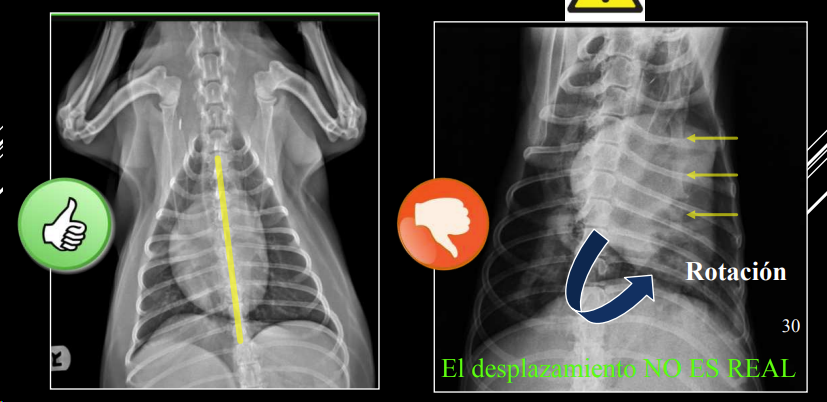

- Alteraciones de posición del mediastino (Desplazamiento mediastino VD)

1. Desplazamientos

- Artefacto (rotación): desplazamiento no real. Si se ve el esternon está mal

- Por enfermedad pleural (neumotórax): desplazamiento no real.

- Masa mediastínica: desplazamiento real.